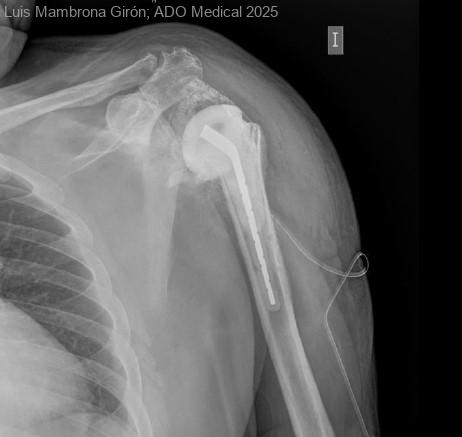

LUXACIÓN PRÓTESIS INVERTIDA DE HOMBRO

Varón de 67 años intervenido de artroplastia de hombro (prótesis invertida) en contexto de fractura proximal de húmero compleja previa (2023). Inicialmente, durante el proceso de Rehabilitación presenta una evolución satisfactoria con un balance articular activo...